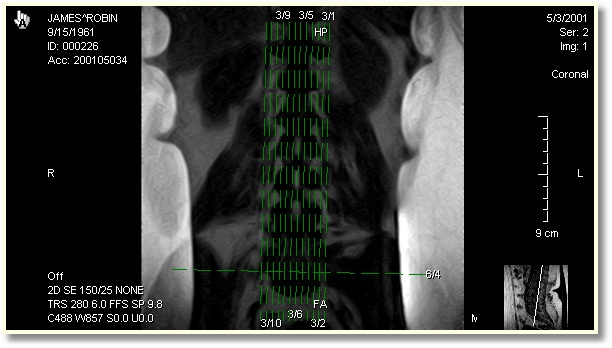

Show All Scout Lines displays scout lines referencing all images within the study. Lines referencing the highlighted image will be displayed in yellow, while all others will be shown in green. Show Active Scout Lines will only show the scout line referencing the currently highlighted image. Show Visible Scout Lines will show Scout Lines referencing all currently visible images. Show Selected Scout Lines will only show Scout Lines referencing images that are currently selected. Remove Scout Lines will not display any scout information.

Each Scout Line has the associated series and image number written beside it.